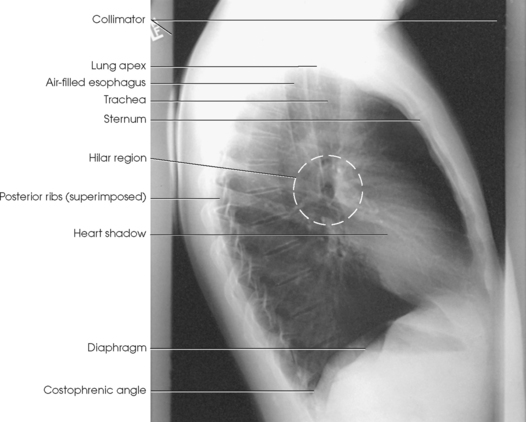

• To determine rotation, examine the posterior aspects of the ribs. Radiographs without rotation show superimposed posterior ribs (see Figs. 10-12 and 10-13).

Structures shown: The preliminary left lateral chest position is used to show the heart, the aorta, and left-sided pulmonary lesions (Figs. 10-37 and 10-38). The right lateral chest position is used to show right-sided pulmonary lesions (Fig. 10-39). These lateral projections are employed extensively to show the interlobar fissures, to differentiate the lobes, and to localize pulmonary lesions.